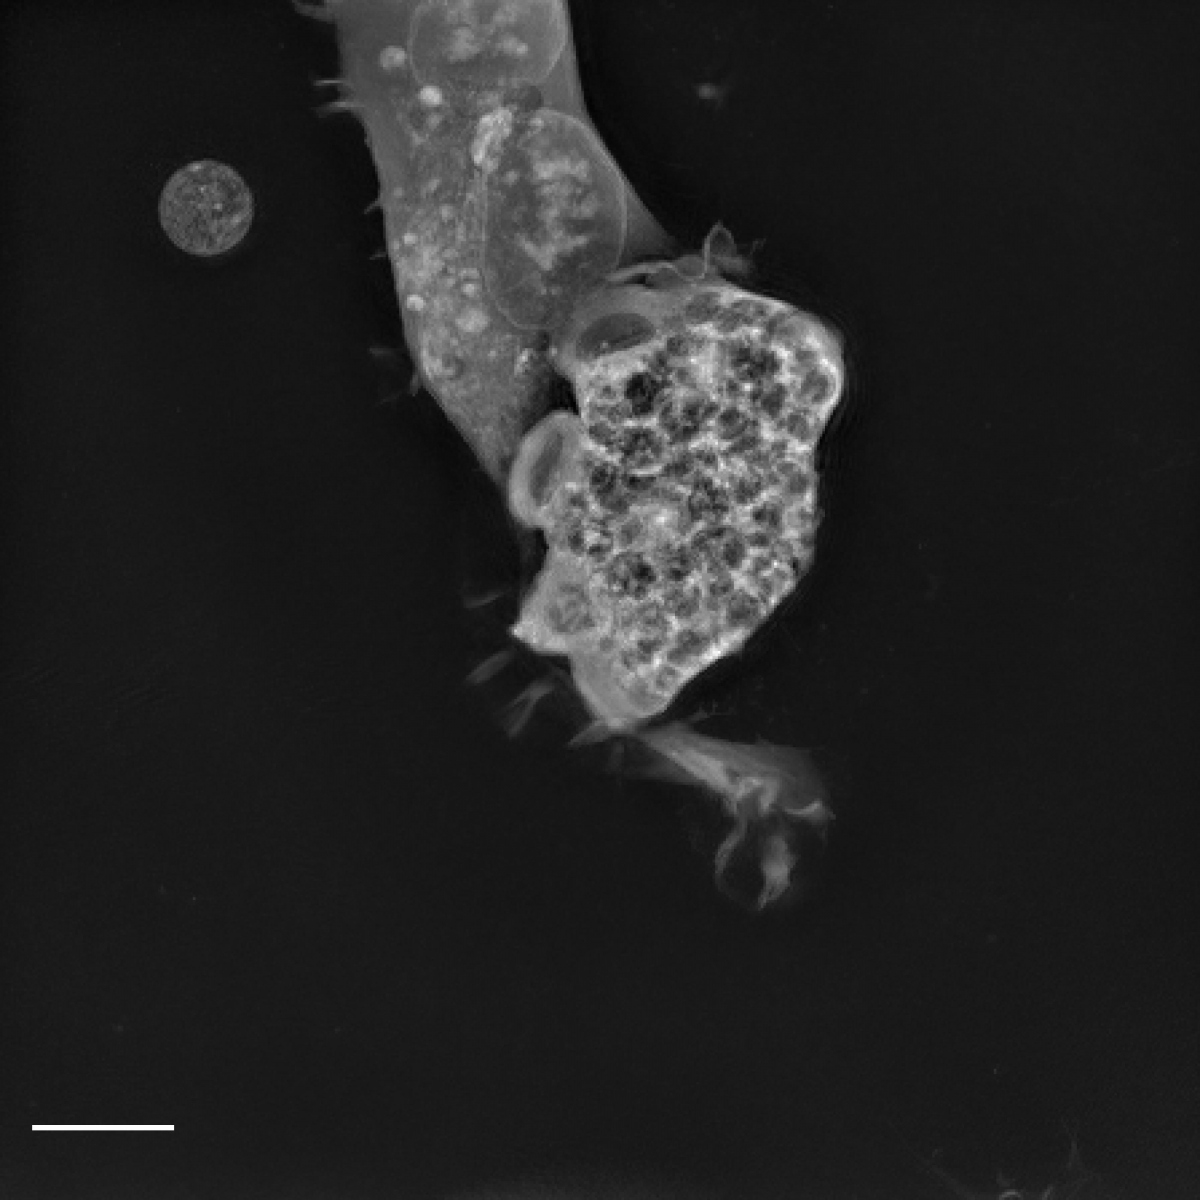

První nemocí, proti které se podařilo najít potenciálně průlomovou terapii, je PAM. Způsobuje ji smrtící mikrobiální patogen Naegleria fowleri. Lidé se touto teplovodní „mozkožravou" amébou infikují většinou při plavání nebo jiných rekreačních aktivitách ve vodě.

Skrze nosní sliznici a čichový nerv může améba napadnout lidský mozek. Ačkoli toto onemocnění není příliš časté (v USA bylo doteď zaznamenáno méně než 200 případů), je i přes veškerou moderní lékařskou péči z 97 % smrtelné. Příznaky začínají obvykle pět dní po expozici a pacienti po několika dnech podlehnou poškození mozku.

Róbert Šuťák a Martin Zoltner založili výzkum na inovativním pokusu využít některé známé sloučeniny, například akoziborol účinný proti spavé nemoci. Jeho účinek proti PAM však nebyl dostatečný. Až díky spolupráci s Lukášem Wernerem a Janem Štursou, medicinálními chemiky z Biotechnologického ústavu AV ČR v centru BIOCEV, se podařilo najít příbuznou molekulu, která byla schopna zabíjet kultivované améby.

„To, že jsme mohli prokázat vyléčení PAM na experimentálním zvířecím modelu, bylo skvělé," dodává Róbert Šuťák. „Experimentální léčba buď významně prodloužila přežití, anebo dokonce myši infikované patogenem Naegleria fowleri vyléčila.“